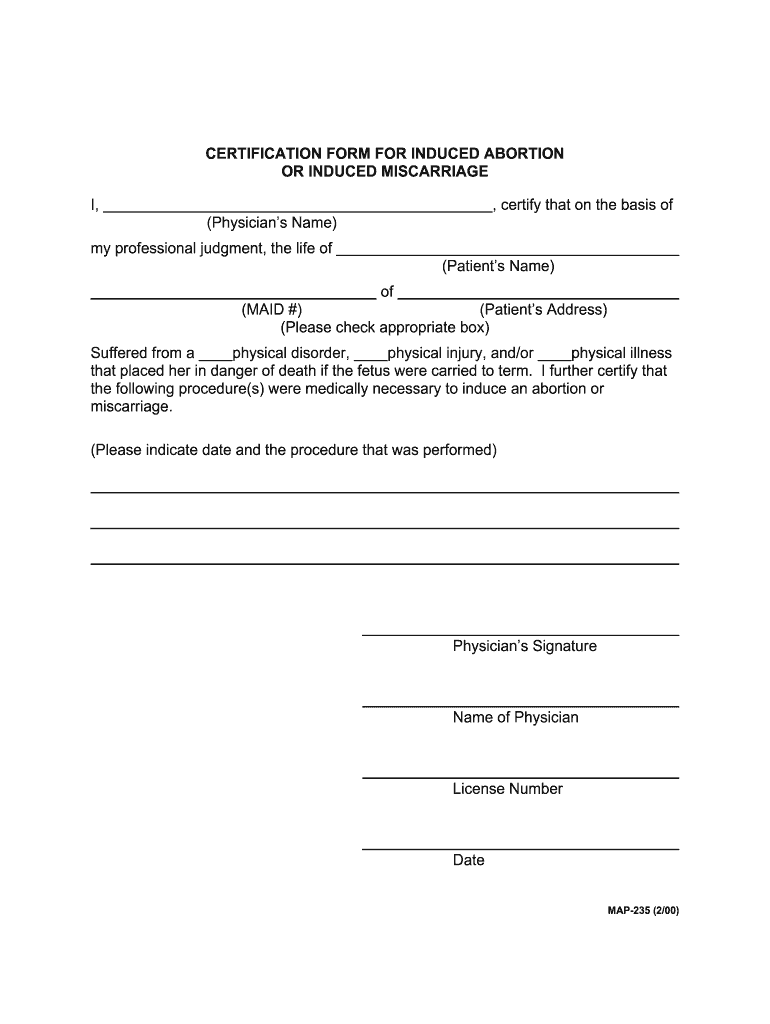

How to tell if you’re having a miscarriage. A lab can examine the tissue to check for signs of a miscarriage. When a miscarriage is confirmed, you'll need to talk to your doctor or midwife about the options.

Miscarriage is commonly diagnosed using a combination of tests, the most standard of which include the hcg blood test, an ultrasound, fetal heart scanning, and a. Passing tissue or blood clots from the vagina. You can practice diaphragmatic breathing at any point after a pregnancy loss, and you don’t even have to get out of bed to do it effectively.